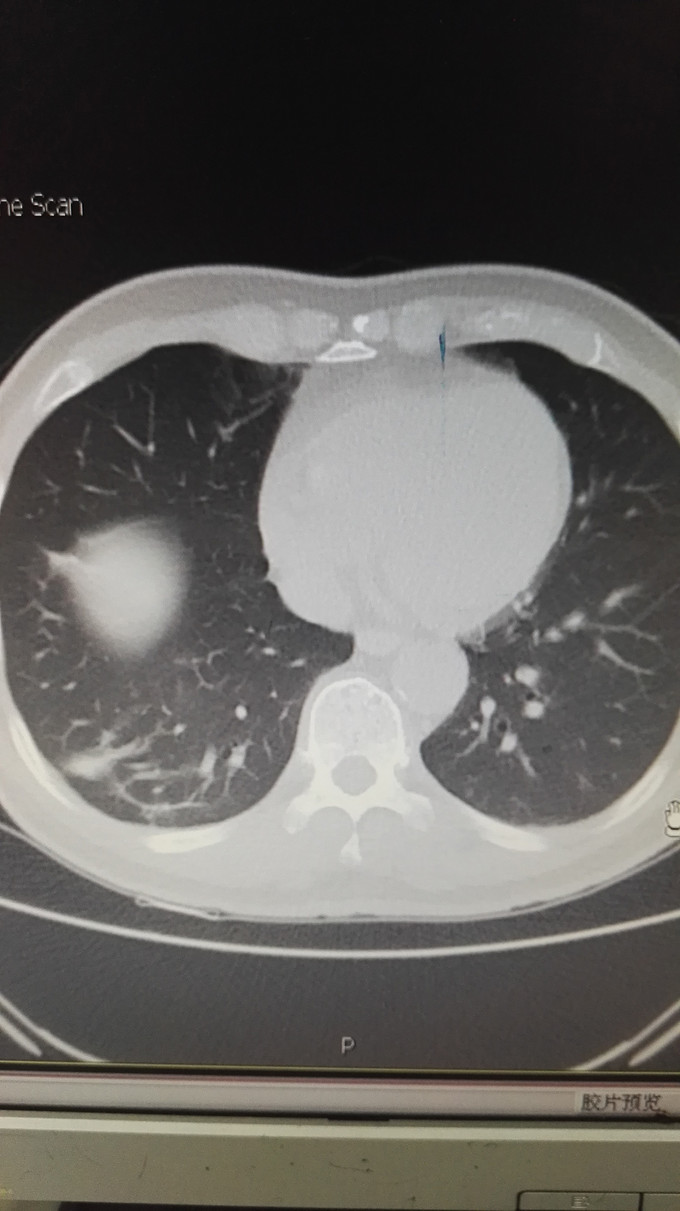

患者男,65岁,退休人员,因体检发现双肺阴影 半月入院。无不适症状。不嗜烟酒,有高血压、糖尿病史。

查体未见异常。 辅助检查:血常规、肿瘤指标、免疫指标、肝肾功能、痰涂片均未见异常。PCT、CRP不高。CT如图:右肺下叶多发斑片状影,左肺上叶蛇段、下叶少许条索状影,考虑双肺慢性炎症。

诊断:双肺阴影查因:肺炎? ; 高血压病 ;2型糖尿病 治疗,目前先进行抗感染及控制血压、血糖处理。